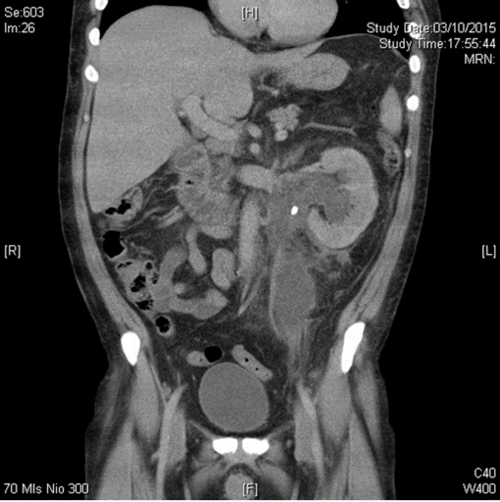

Case 3

A 42-year-old woman presented with left loin pain radiating to the left iliac fossa, pyrexia and feeling generally unwell with spontaneous decompression of the pelvicalyceal system. Her inflammatory markers (WBC, CRP) and serum creatine were raised and she looked unwell.

- What would be your approach to decompress this?

- Name two major complications associated with the percutaneous approach.

-

The drainage of acute renal obstruction, especially when suspected to be associated with infection, is a urological emergency. Obstruction can be drained by either retrograde ureteric stent (RUS) insertion or percutaneous nephrostomy (PCN). Current guidelines do not provide specific recommendations on the choice between these options [3,4]. This particular patient had a retrograde stent inserted followed by a percutaneous drain in the retroperitoneal collection with broad spectrum antibiotic cover.

Quality improvement guidelines for percutaneous nephrostomy recommend a major complication rate of <4% which is achievable [5] although most series report combined major and minor complication rates of approximately 10% [4]; these include severe bleeding, renal loss and septic shock. Reference 5 provides a usefully detailed overview on the subject.